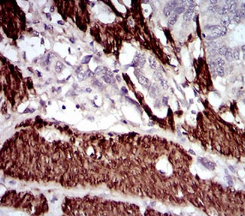

Calponin h1 (CN) is a differentiation marker of smooth muscle cells that has been reported to be down-regulated in the blood vessels of several human tumors.

IHC    1/100 - 1/500